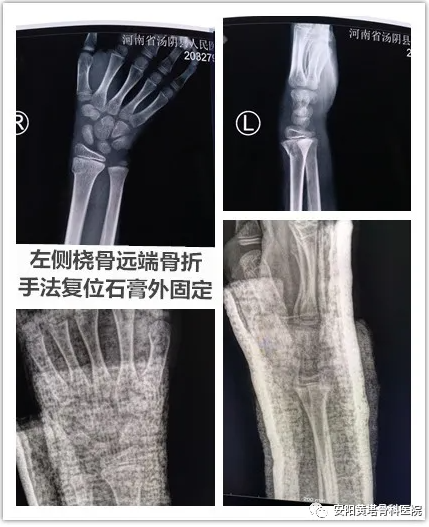

【安陽黃塔骨科醫院】9歲患者左橈骨遠端骨折+左側肱骨遠端粉碎性骨折病例分享

例分享:患者男,9歲,左橈骨遠端骨折,左側肱骨遠端粉碎性骨折;予以左側橈骨遠端手法復位石膏外固定,左肱骨遠端粉碎性骨折閉合復位內固定術,手法正骨與微創技術相結合,避免開刀手術,減少患者痛苦,縮短恢復周期。